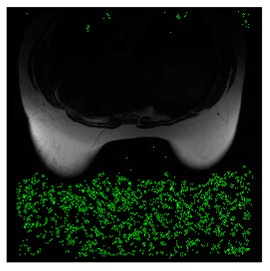

4.3. The Results

In this subsection, we describe three experiments used to measure the performance of the proposed method. The first experiment shows the stegoimage and marks the pixels’ positions that have been modified during the embedding process, as shown in Table 2, Table 3, Table 4, Table 5, Table 6 and Table 7. To make modified pixel positions have a pronounced effect, we set bpp (bit per pixel) rate at 0.05 and 0.025. It can be seen from the results that the proposed local complexity function can distinguish ROI and RONI from most of the medical images, so modified pixels are mainly gathered in RONI. However, it is observed that the proposed local complexity function cannot distinguish between ROI and RONI in the Prostate-MRI database due to the relative complexity of the image. Besides, “Modified BPP” represents the proportion of pixels in the image that have been modified. We observed that the performance of “baboon” in the grayscale standard images database is poor because that image’s pixels are relatively complex. It becomes challenging to select the more embeddable pixels based on the proposed local complexity function. Nevertheless, the modified pixel positions in other grayscale standard images, such as Lena and Barbara, are relatively smooth, verifying that our local complexity function is also applicable to general images.